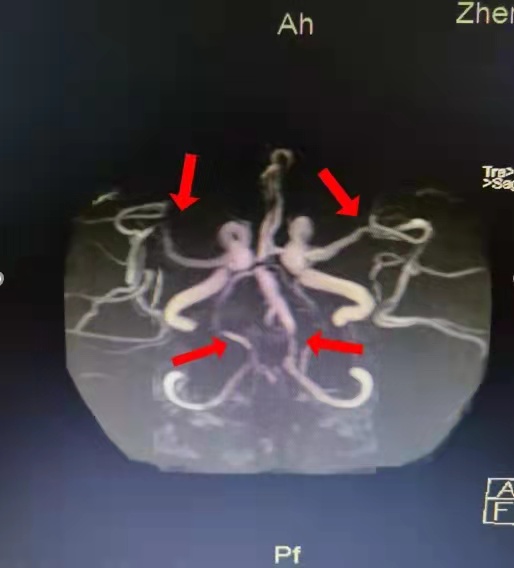

病例2 患者为男性,22岁,在全麻状态下进行手术。术后,患者出现左侧肢体无力、反应迟钝、记忆力下降,来到郑州大学第二附属医院就诊。头颅磁共振检查结果提示:右侧额顶叶大面积脑梗死,双侧颈内动脉末端重度狭窄及闭塞。脑动脉造影检查结果提示烟雾病。若有此病,患者在儿童时期即可出现脑梗死,有偏瘫、肢体麻木、复视等表现;成年后,还易发生脑出血,给患者及家庭带来极大痛苦和负担。对于此病,早期发现,可进行血管重建手术,恢复脑血流,避免后期发生卒中的风险。